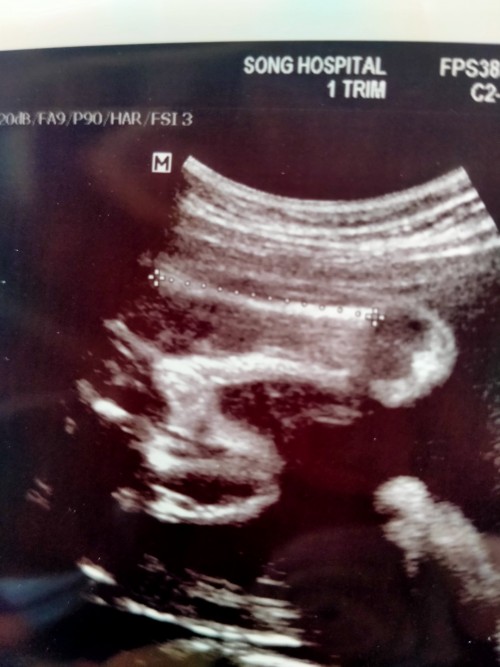

เห็นเพศกันตอนกี่Wคะแม่ๆ

ของเราตอนนี้ 14 W อาทิตย์หน้าหมอนัดฟังผลเลือด ลุ้นมากจะได้ช.หรือญ.แม่ๆเห็นเร็วสุดกี่Wคะ